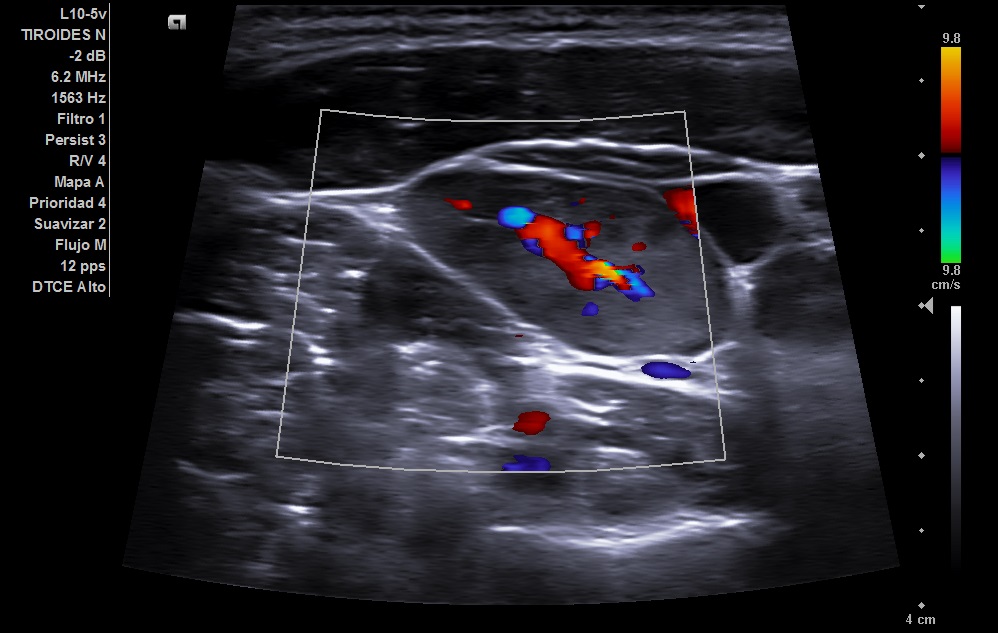

Se realizó en consulta una ecografia clínica, se colocó al paciente decúbito supino con ligera hiperextensión del cuello y tras palpar el bultoma se localizó con la sonda. Visualizamos en nivel 1 una imagen hipoecogénica ovalada de 22 mm con alteración de la estructura pero con hilio graso conservado y con aumento de vascularización compatible con adenopatía reactiva.